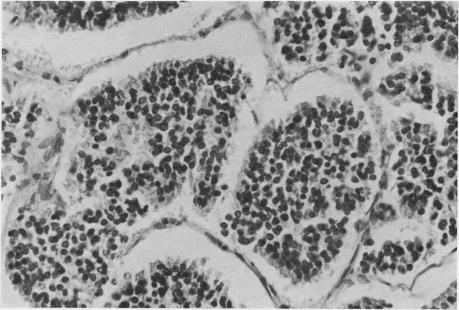

In 9 years in Kenya, 34 examples of primary liver cancer wer diagnosed in patients in the first two decades of life. This represents 4.7% of all liver cancers during this period. The larger proportion (29) were hepatocellular carcinoma. In the second decade, there was a notable association with macronodular cirrhosis. Analogy with experimental work suggests that cells in mitotic cycle may be more vulnerable to the effect of environmental carcinogens. Five examples of hepatoblastoma were identified at ages from 2 months to 14 years; none showed the features of "mixed" tumours. The ratio of hepatoblastoma to hepatocellular carcinoma was the reverse of that found in other large series of juvenile hepatic tumours. The histopathological features of these tumours are described and problems of their classification are discussed.

在肯尼亚的9年里,34例原发性肝癌在20岁之前的患者中被诊断出来。这占该时期所有肝癌的4.7%。其中较大比例(29例)为肝细胞癌。在第二个十年中,与大结节性肝硬化有显著关联。与实验工作的类比表明,处于有丝分裂周期的细胞可能更容易受到环境致癌物的影响。在2个月至14岁的年龄段中发现了5例肝母细胞瘤;均未表现出“混合”肿瘤的特征。肝母细胞瘤与肝细胞癌的比例与其他大量青少年肝脏肿瘤系列中的情况相反。描述了这些肿瘤的组织病理学特征,并讨论了它们的分类问题。